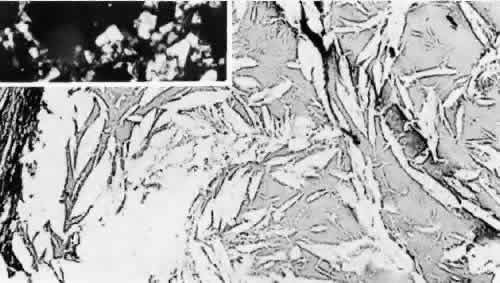

The clinical observation of synchysis scintillans is relatively rare because old trauma usually leads to fibrosis and other secondary changes, in addition to the hemorrhage, and the crystals may not be visible. Histologically, however, cholesterol crystals are frequently found as a sequela of old intraocular hemorrhage (Fig. 7). The cholesterol dissolves out during processing, leaving slit-shaped clefts. Frequently, these elicit a foreign body giant cell reaction.52

Fig. 7. Clefts in the vitreous represent areas in which cholesterol crystals had resided before processing of the tissue dissolved them out. Inset. Birefringent cholesterol crystals obtained from the anterior chamber fluid in an eye with cholesterosis bulbi. (main figure, hematoxylin and eosin, original magnification, × 40; inset, unstained, polarized, original magnification, × 10)